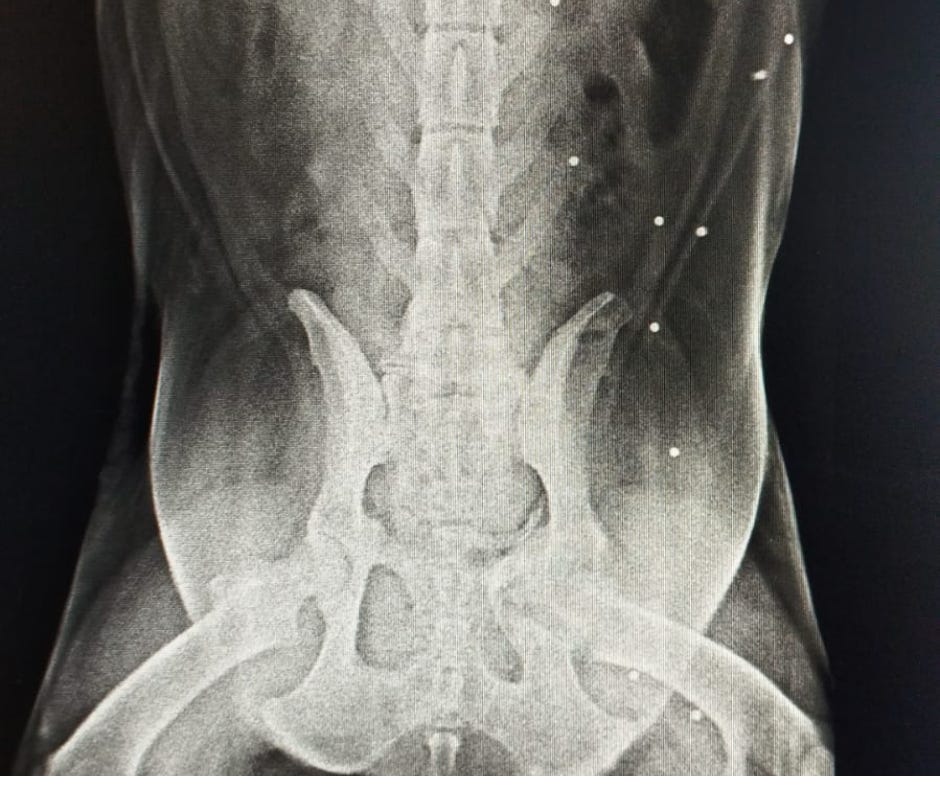

Because Lucy was experiencing difficulty standing, she needed an X-ray to determine the underlying issue.

With the X-ray results, they hoped to identify any abnormalities or injuries that could be causing her discomfort. This step was crucial in creating an effective treatment plan to help Lucy regain her strength and mobility.

Lucy's X-rays unveiled a troubling skeletal issue, and the presence of pellets indicated that she had been shot multiple times.

The exact cause of her present problem remained unclear; she might have been struck by a vehicle or subjected to physical assault.